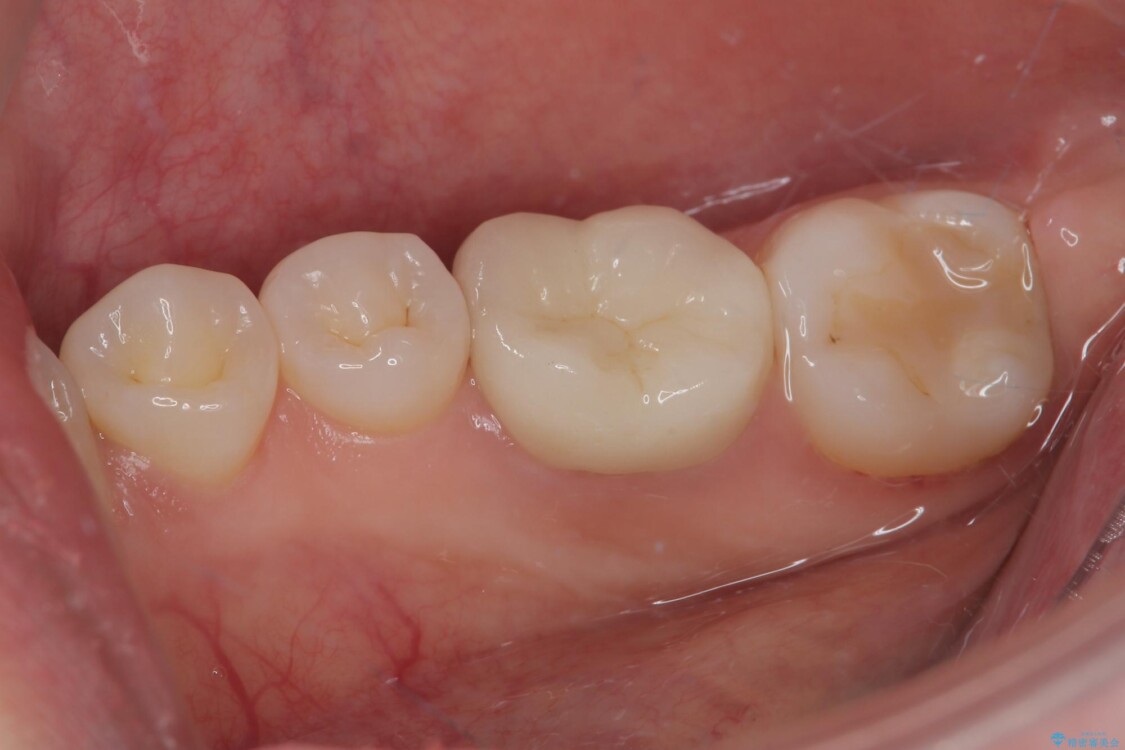

治療後

• ラバーダム使用で再感染リスクを抑えた再根管治療+精密な補綴による長期安定を実現 治療後画像